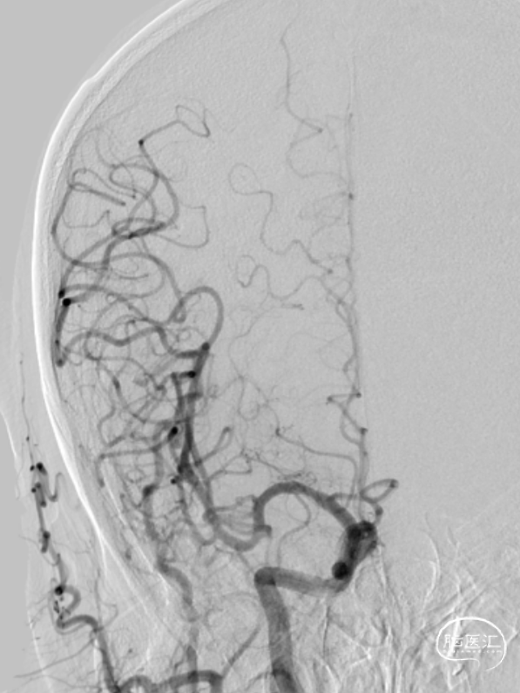

沿导丝置入4*30mm AVIATOR PLUS球囊预扩张狭窄病变,狭窄改善欠佳,再用6*30mm AVIATOR PLUS球囊扩张病变后置入9*40mm PRECISE支架并释放。

3

支架植入后可见贴壁良好,能够顺应迂曲的血管走形,置后残余狭窄约30%,颈内动脉血流通畅,同侧大脑前显影。为避免高灌注,不再予以后扩张。

观察患者体征稳定,支架形态良好,撤出器材,使用Exoseal封堵止血系统封堵股动脉穿刺点后,结束手术。患者愈后良好。

对于重度狭窄的颈动脉,因长期低灌注,往往导致狭窄远端血管腔塌陷,远近端血管直径差别较大。由于支架直径需要根据颈总动脉的直径来选择,为了避免颈内动脉被过度扩张,术者多数情况下会首选锥形支架,以追求支架良好的贴壁性及安全性。PRECISE作为一款自动锥形颈动脉支架,有良好的贴壁性及对于不同直径血管的适应性。从以上两例手术可以看出,支架远近端贴壁良好,血流通畅,远端血管并未表现出oversize所担心的血管扩张过强,甚至导致夹层的情况,充分体现了PRECISE支架的顺应性特性。